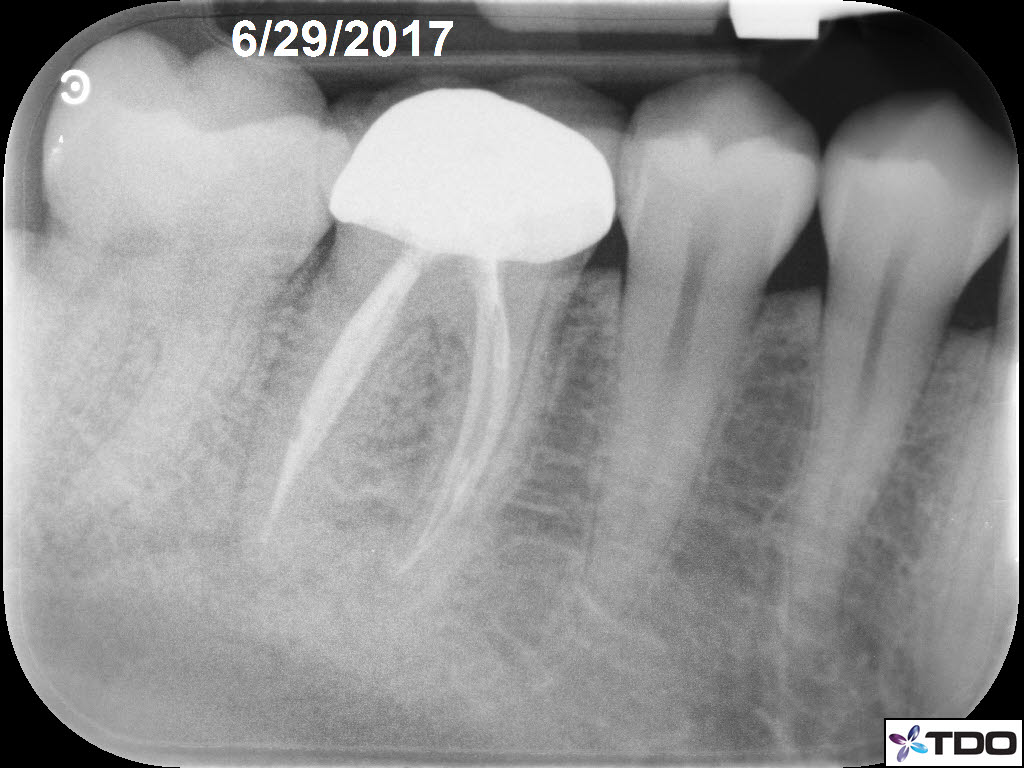

In the hierarchy of dentin conservation the existing restorative has the lowest priority and it quite frankly gets in the way of our access to the root canal system. But, after practicing directed dentin conservation for a while, you sometimes get lucky. The patient is 40yo. She was symptomatic at the time of treatment and interestingly the mesiobuccal canal was partially vital while the mesiolingual, distobuccal and distolingual canals were partially necrotic. She was asymptomatic at the completion visit as well as at the follow-up appointments.

Hi Gergely. The crown was less than two weeks old when the patient was first seen in my office. The previous crown was 15 yrs old and was seldom sensitive; the RD replaced the crown due to an “open margin.” Heat/cold sensitivity ensued after the crown prep. Four days after the permanent crown was cemented the patient woke up with severe throbbing pain and the temp sensitivity became worse. When she presented to my office she reported severe biting tenderness and tender submandibular lymph nodes.